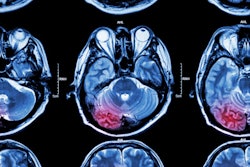

Her group sought to explore CVR reactivity any links between impairment and tissue damage and the progression of such damage one year after stroke diagnosis. They conducted a study that used data from the university's Mild Stroke Study 3 (MSS3), which recruited 182 small-vessel disease patients with minor ischemic stroke (stroke score of 1 out of 4). Within three months after having a stroke, the patients presented for baseline 3-tesla MR imaging, which the researchers used to quantify CVR reactivity; they returned for follow-up after a year. MRI exams visualized patients' intermittent breath intake of carbon dioxide (CO2) gas and medical gas to map CVR and acquired blood oxygen level-dependent images.

Research from the University of Edinburgh presented at the ISMRM annual meeting found that MRI links cerebrovascular reactivity and small-vessel disease in mild stroke patients. Here, data shows that those with lower reactivity have higher volumes of white matter hyperintensity and perivascular spaces. Image courtesy of Emilie Sleight.Patients with lower CVR reactivity at baseline had higher white matter hyperintensity volumes and a higher number of lacunes and microbleeds, the group reported, but there were no significant differences in brain volumes or perivascular space volumes between high and low CVR activity.

For longitudinal analysis, one year after baseline analysis, the team included data from 163 patients with median small-vessel disease score of two. It found increased white-matter hyperintensity volumes in those with lower CVR, suggesting underlying damage that was not visible at baseline imaging. These results remained true even after adjusting for factors such as sex, age, and vascular risk. Additionally, it reported that those with lower CVR reactivity at baseline saw a significant increase in perivascular space volume.